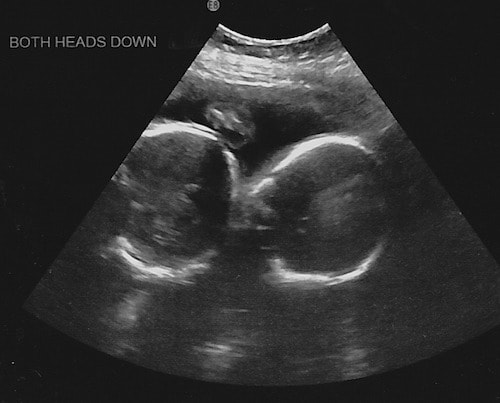

- Ultrasound Photos at 24 Weeks Pregnant With Twins

Ultrasound Photos at 24 Weeks Pregnant With Twins